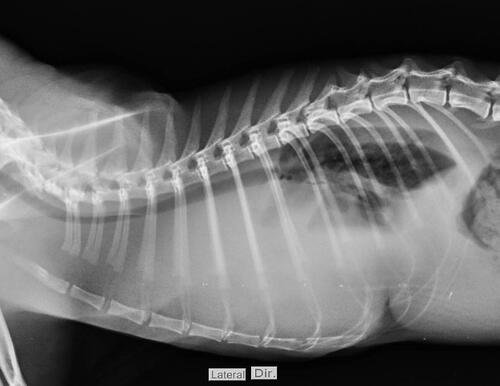

Essa vaquinha é para custear o tratamento do nosso pequeno Loki. Ele é um gatinho lindo que gosta de carinho (quando ele quer) e que ama subir em tudo que pode. Notamos que o Loki estava emagrecendo, e no dia 22-06 ele acordou muito ofegante, com isso levamos para o hospital veterinário saude animal aqui em Maringá-PR. Lá foi constatado que havia líquido no pulmão, e por isso ele estava sem conseguir respirar. Foi feito todo o tratamento para retirada do líquido, analises e exames. Essa primeira parte conseguimos pagar com os limites dos cartões que temos, mas infelizmente chegou a notícia que temiamos.

Loki foi diagnosticado com FELV e devido a essa doença um linfoma apareceu em seu pulmão, hoje Loki está medicado e melhor, mas para que possa sobreviver será necessário uma série de quimioterapias, aproximadamente 4 meses de tratamento. O valor da quimio que deve ser feita semanalmente é R$ 300,00 reais, além disso ele deve realizar exames de Raio X a cada 15 dias e hemogramas para acompanhar a diminuição do tumor. Incluindo os custos com medicação precisamos do valor de R$ 6 mil reais para o tratamento completo, para que o Loki tenha uma chance de viver mais alguns anos. Contamos com a ajuda de todos vocês nessa luta, o Loki é parte da nossa família, e não conseguimos imaginar a nossa vida sem ele.